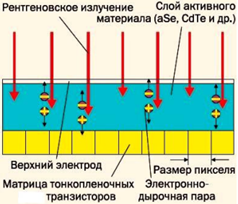

Существует два вида преобразования рентгеновского излучения в электрический сигнал:

2. Прямое – рентгеновское излучение сразу преобразуется в электрический сигнал.

Такие плоскопанельные детекторы оснащены фотопроводником из аморфного селена (a-Se), который самостоятельно захватывает рентгеновские фотоны и преобразует их в электрический заряд.

Плоскопанельные детекторы прямого преобразования стоят существенно дороже детекторов непрямого преобразования, они чувствительны к окружающей среде, не переносят резких перепадов температур. Маммографы с такими приемниками предъявляют особые требования к стабильности питающей сети, а завод изготовитель зачастую рекомендует подключать оборудование к электросети лечебного учреждения через стабилизатор напряжения или через источник бесперебойного питания. При этом качество цифровых снимков, полученных с плоскопанельных детекторов прямого преобразования, существенно выше за счет большего соотношения сигнал/шума, больших значений функции передачи модуляции (MTF - Modulation Transfer Function) и квантовой эффективности регистрации (DQE - Detective Quantum Efficiency).